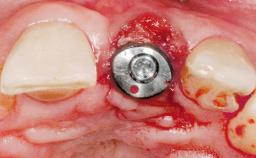

This 43-year-old male patient, a non-smoker, came to our practice because of a fracture of tooth 12 caused by a bicycle accident. Due to the combined para- and infrabony crown and root fracture, tooth extraction, and subsequent implant placement were suggested to the patient as the therapy of choice. The patient had high esthetic expectations with regard to the treatment outcome and asked for an immediate fixed provisional restoration. His individual esthetic risk profile summed up to a medium esthetic risk.

Placement Protocol Immediate implant placement

Bone Volume Sufficient, with intact walls

Loading Protocol Immediate

Retention Screw-retained Screw-retained